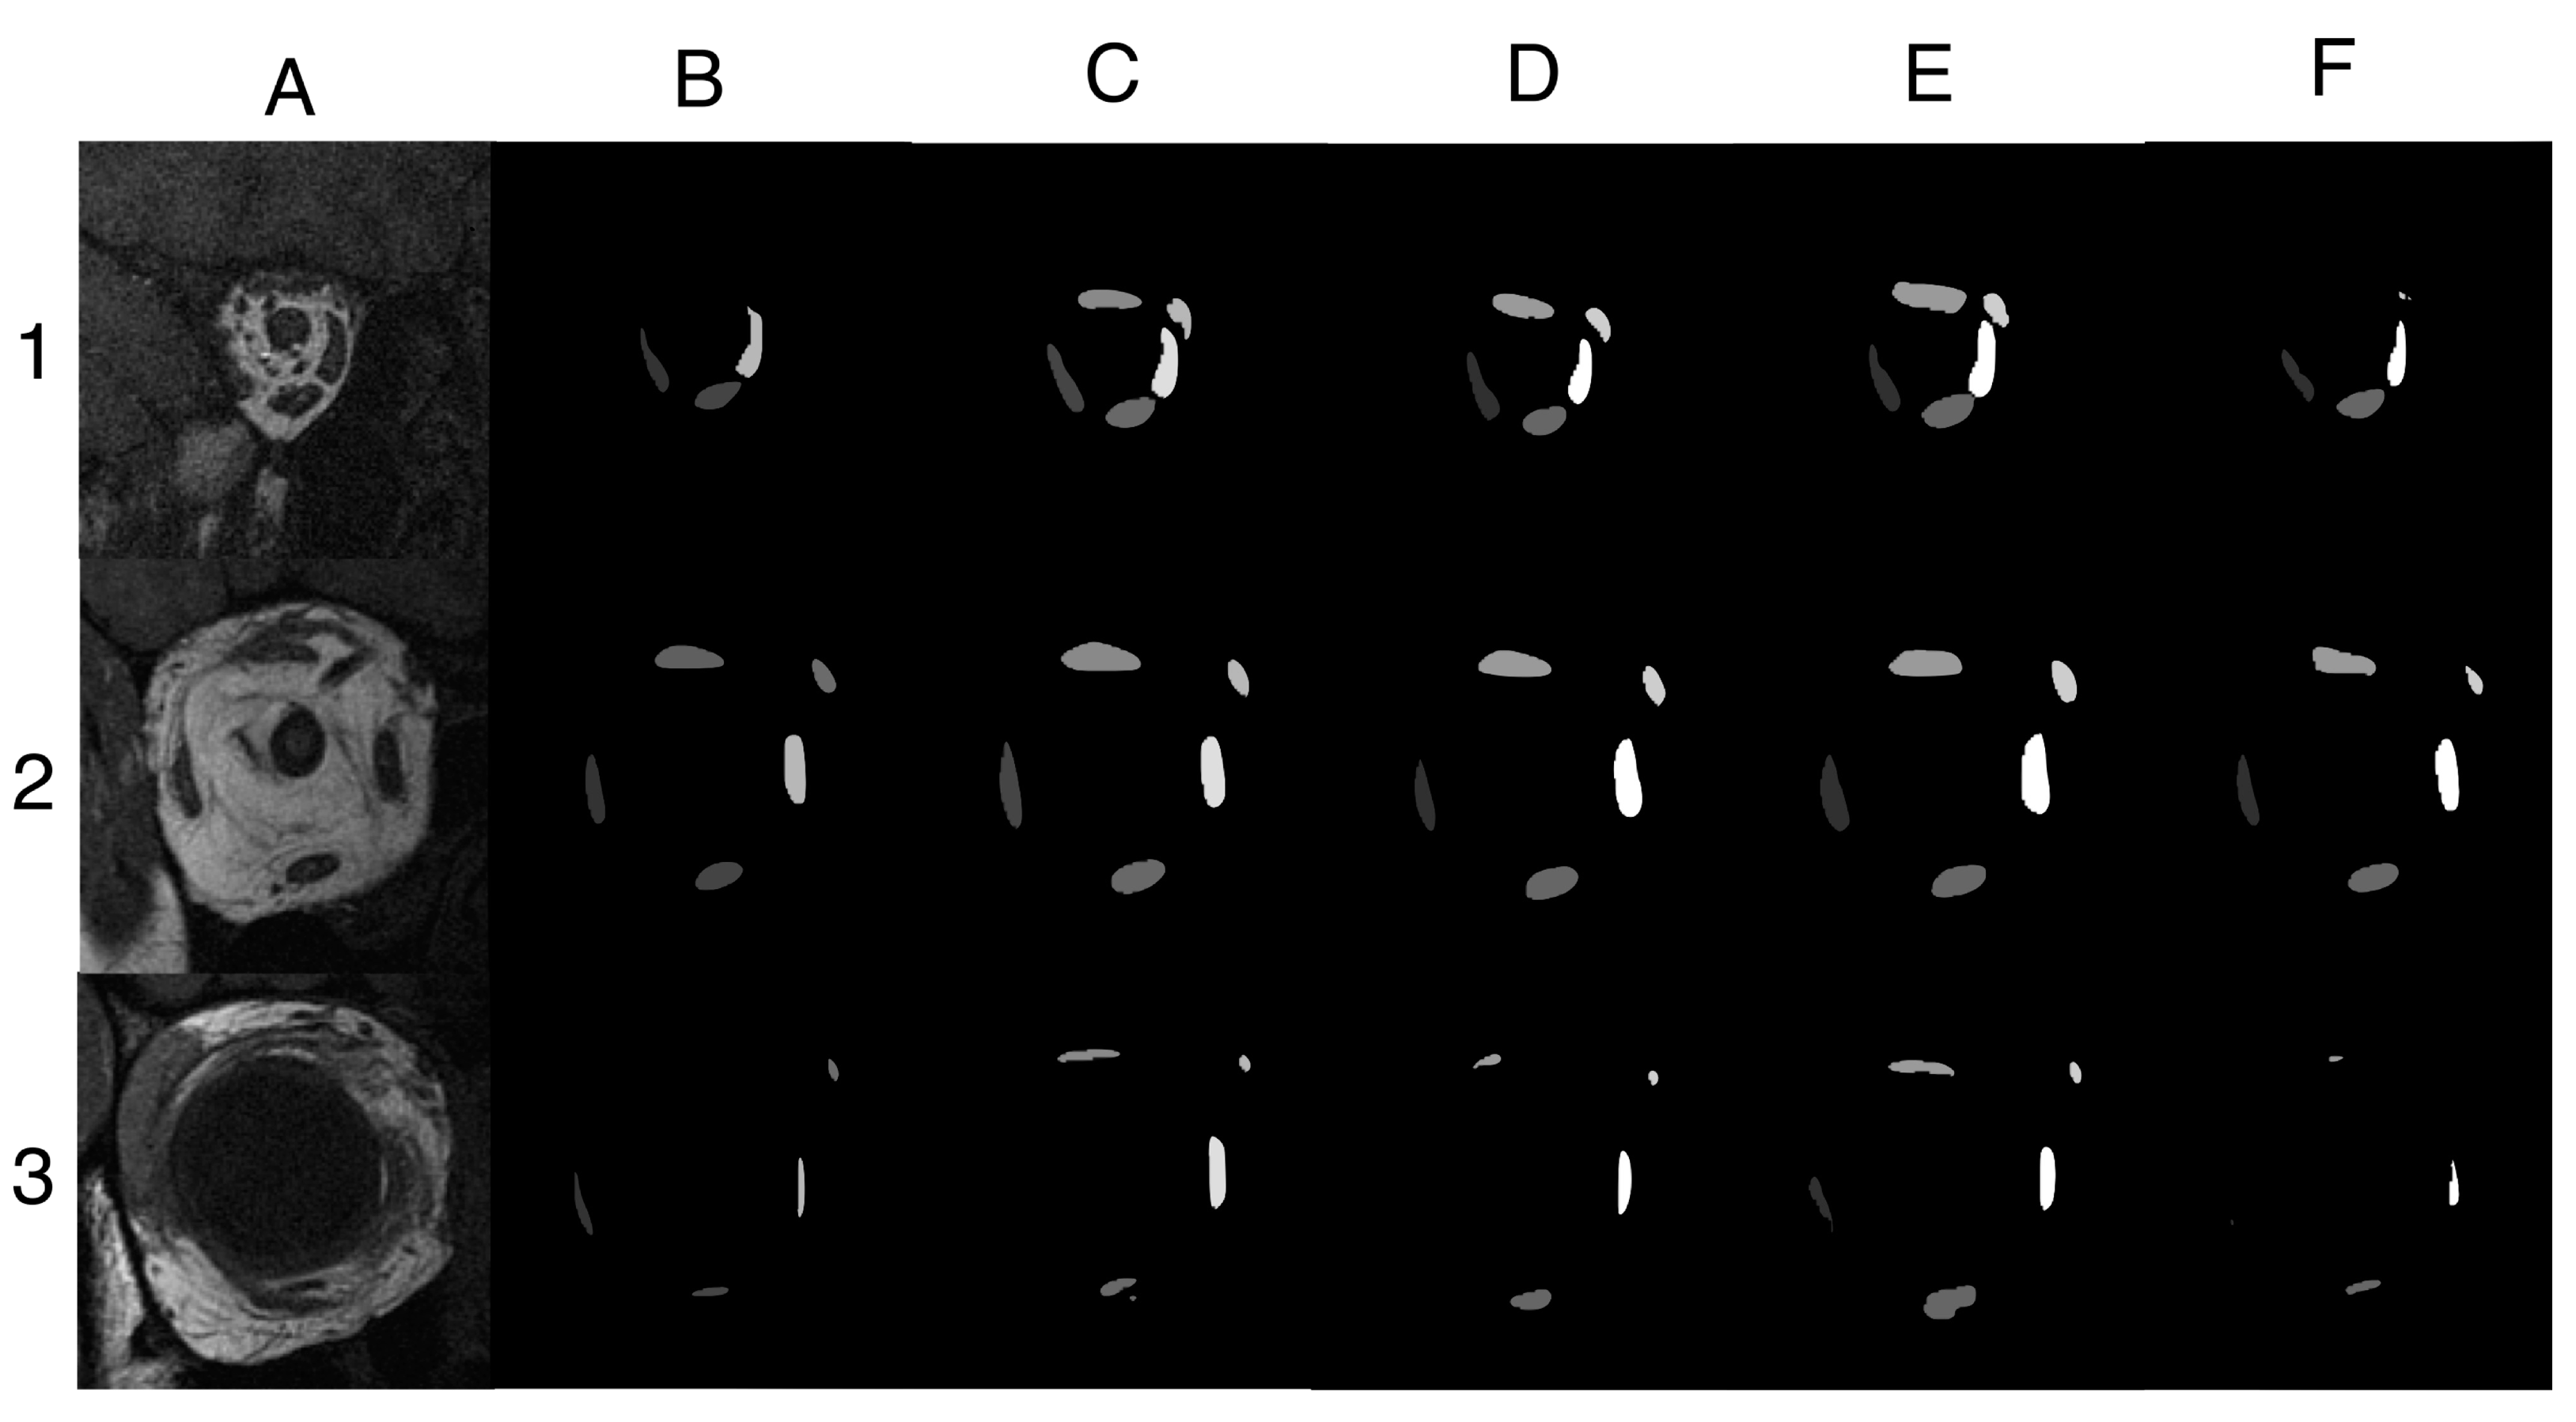

3.1. Assessment of Segmentation Accuracy

3.5. Impact of MRI Slice Location on Segmentation Accuracy